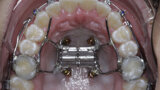

New Age orthodontics and orthopaedics with temporary anchorage devices